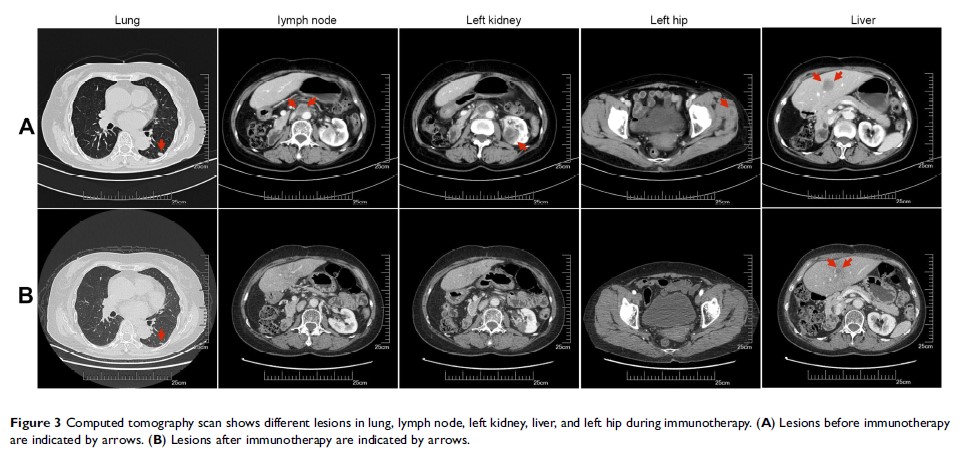

PD-L1 高表达的转移性胆囊癌患者接受 Nivolumab 联合放疗后明显缓解:病例报告